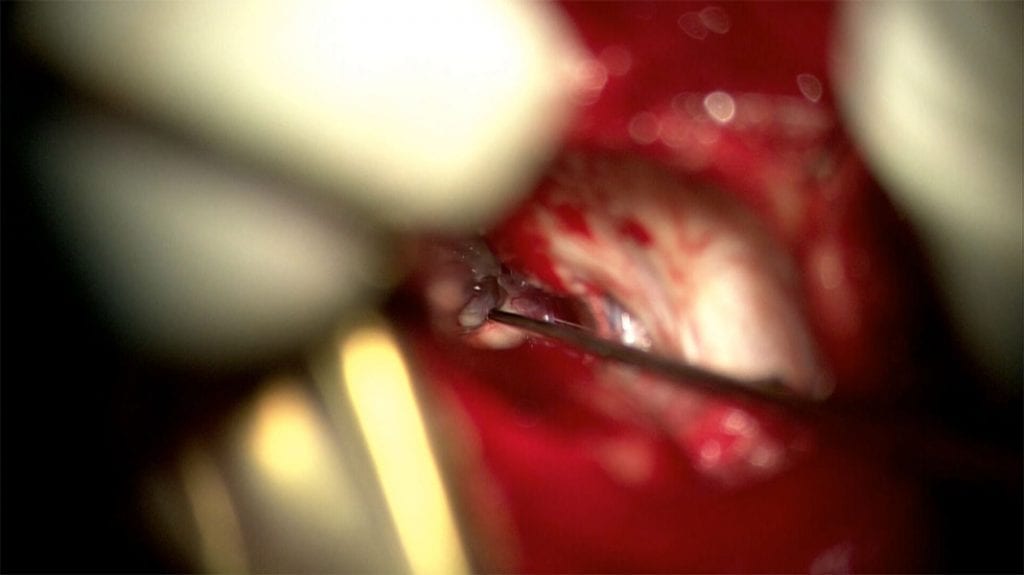

This patient with Trigeminal Neuralgia had surgery in 2012 by another surgeon at another institution. Initially, she felt well, but the pain gradually returned over…